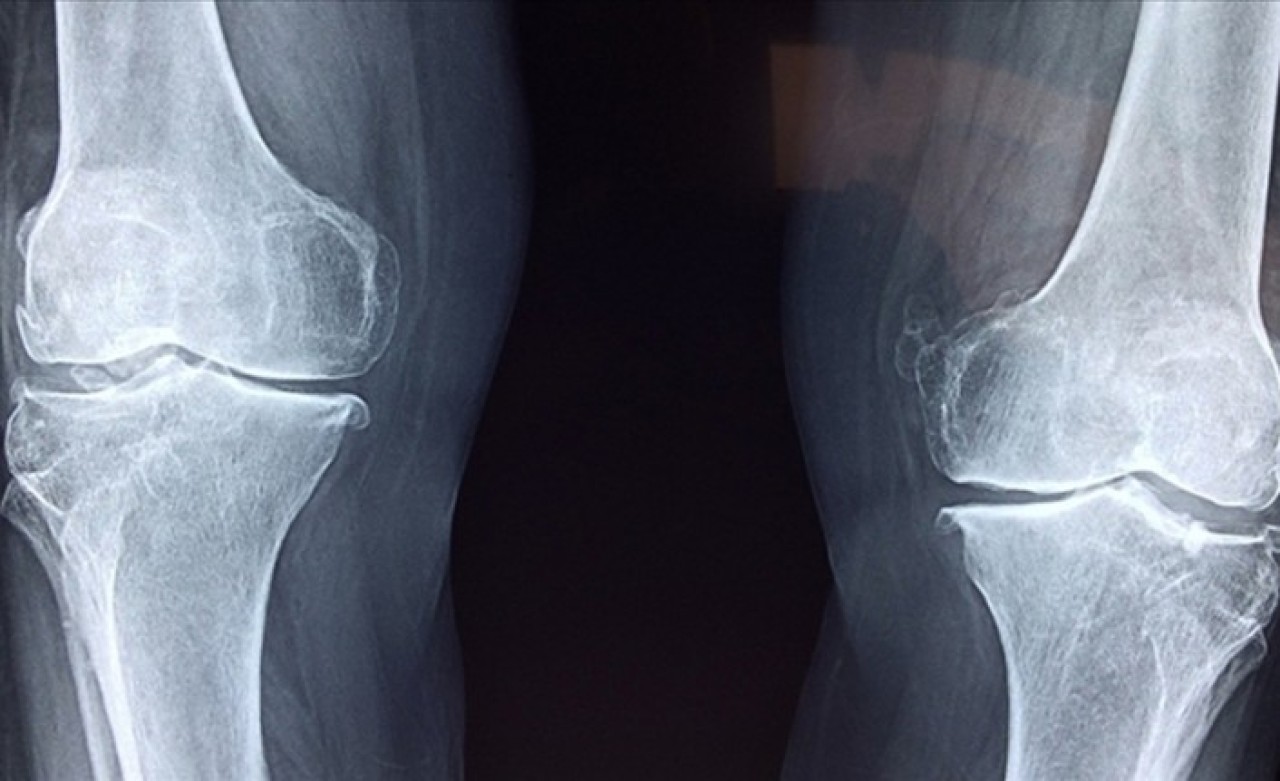

Eklemde, oynak yerlerinde ağrı, şişlik, sabah katılığı-tutukluğu, ısı artışı bazen de kızarıklık olabileceğini aktaran Şahin, şöyle devam etti:

Vücudun kendi kendine saldırdığı romatizmal hastalıklarda tekrarlayan iltihap ataklarının yaşandığını vurgulayan Şahin, "Bu hastalıkların erken tanısında son yıllarda ultrasonografi, tırnak yatağı kapillaroskopisi, tükürük bezi biyopsisi, cilt-kas biyopsileri ve çeşitli diğer doku biyopsileri gibi işlemler yapılıyor. Erken tanı koyup tedaviye başlamak, birçok romatolojik hastalıkta sakatlık ve iş gücü kaybını önlemede önemlidir." ifadelerini kullandı.